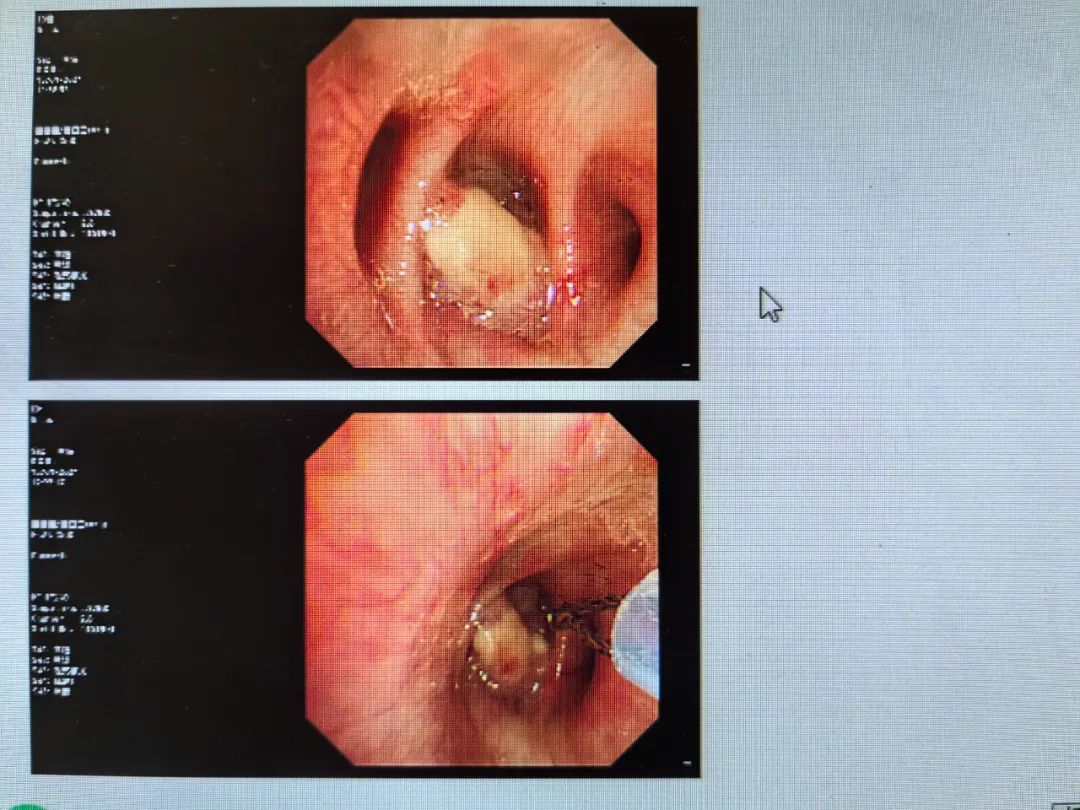

上個月複查,發現右肺下葉又出現了佔位,於是做了PET-CT,提示惡性病變。然後做了支氣管鏡,取了活檢。

“哦,大概率是小細胞肺癌轉移了。”我心裏想,點開了他的活檢報告。

“病理提示:鱗癌。”